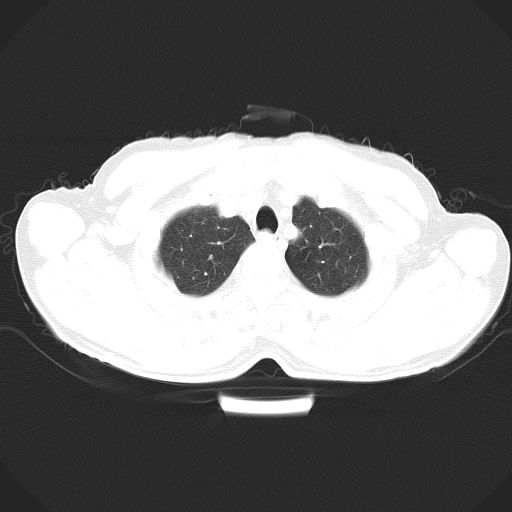

以下是引用心路寻觅在2010-3-1 10:23:00的发言:[br]1、考虑左肺上叶周围型肺癌[br]2、右上肺陈旧性病灶。[br][br][本贴已被 心路寻觅 于 2010-3-1 10:40:18 修改过]

以下是引用shuiyuan在2010-3-1 10:45:00的发言:[br]考虑左肺上叶中心型肺癌伴阻塞型炎症,邻近胸膜受侵。